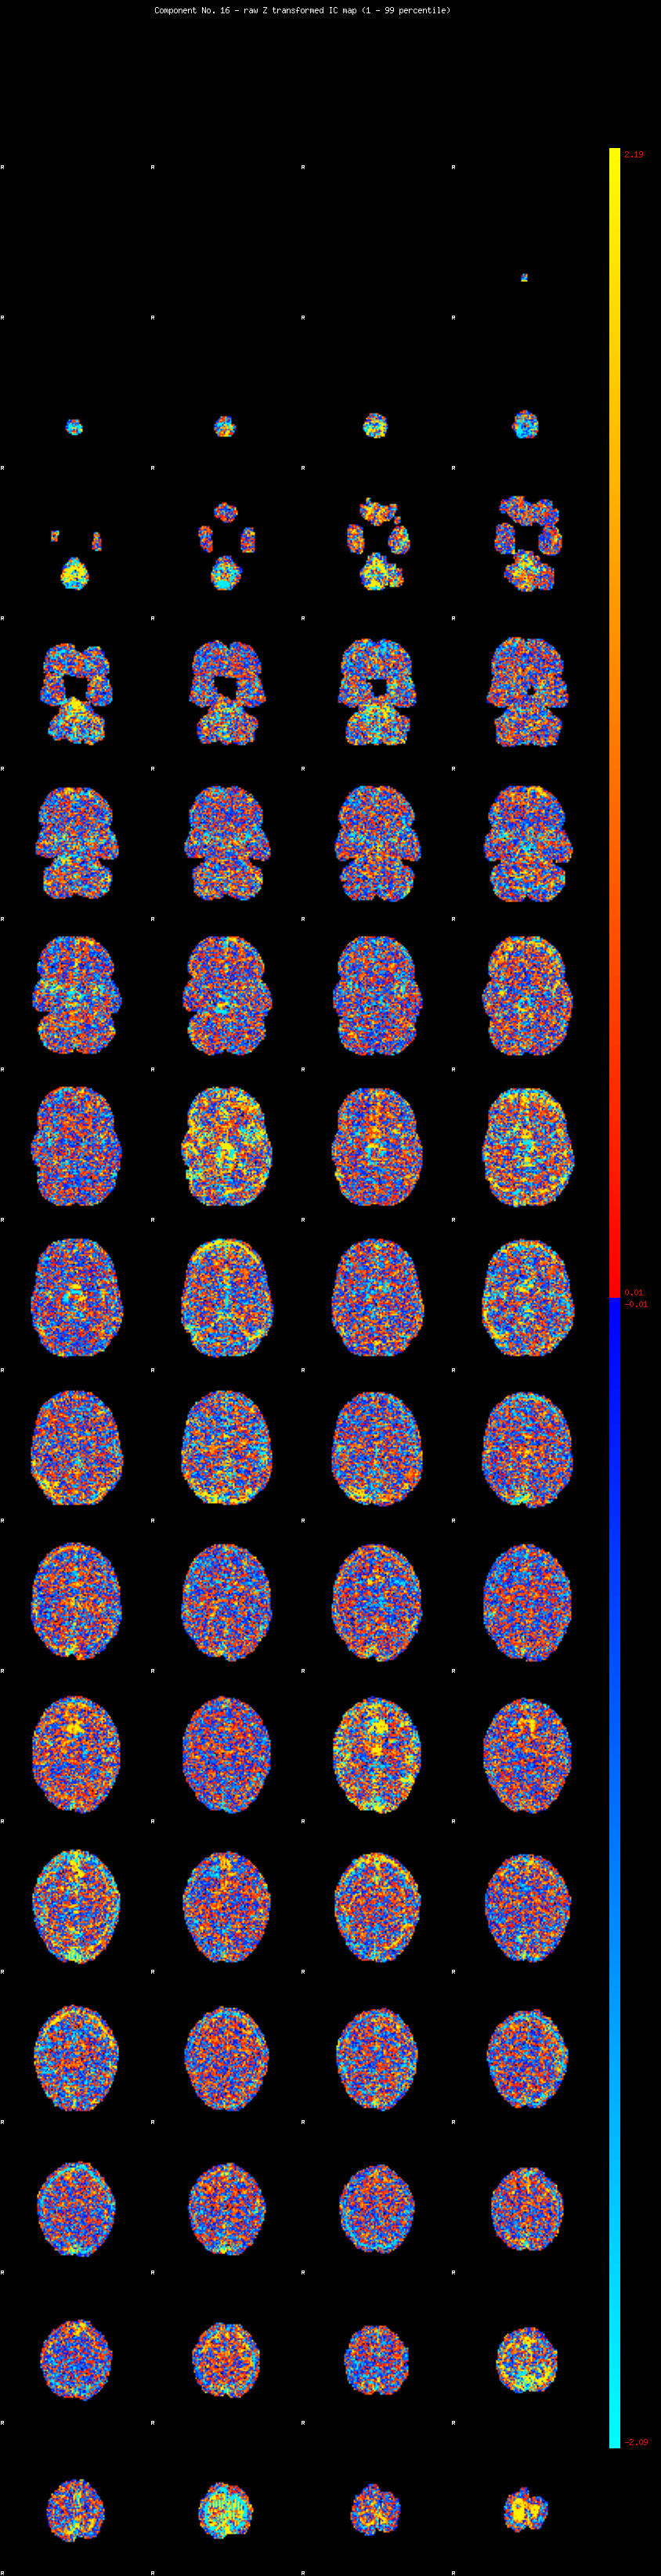

IC_16 Mixture Model fit

Means : -0.000000 3.056889 -2.619884

Vars : 1.000000 4.156003 2.475208

Prop. : 0.915765 0.043173 0.041063